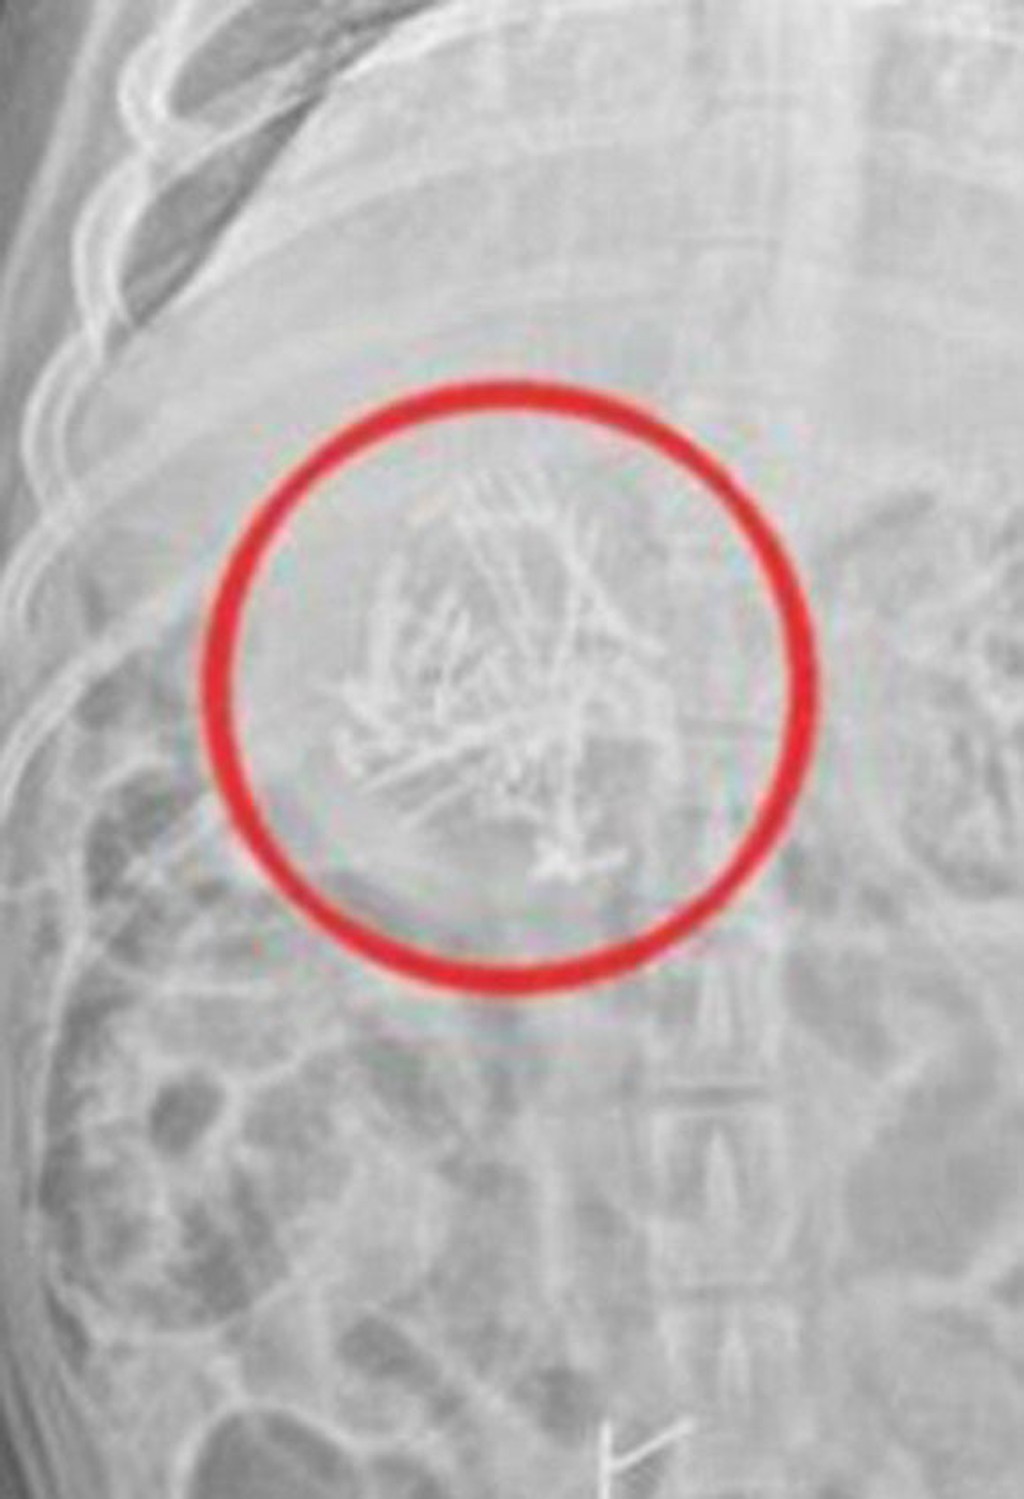

Labrador Reggie si až tak nepochutil. Spolu s ostatnými dobrotami zjedol veľa čokolády, ktorá je pre psov toxická, ale aj viac ako 50 kovových ihiel. Tie sopku držali pohromade.

Matka síce ochránila syna, ale nenapadlo jej, že dcérin projekt zmizne za moment nepozornosti. Dvojročného labradora ihneď odviezli na veterinárnu kliniku. Tam podstúpil operáciu, vďaka ktorej mu všetky ihly vybrali.